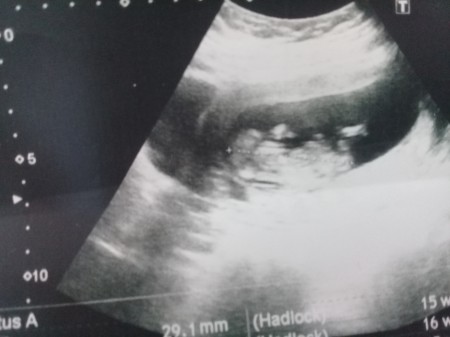

Ultrasyondan cinsiyet anlayasilabiliyormu anlayanlar y

ardimci olabilirmi